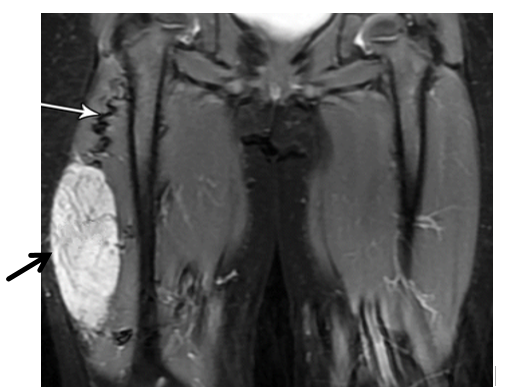

An incisional biopsy was performed under general anesthesia. Microscopic examination revealed  tightly packed spindle-shaped cells, irregular nuclei, few dividing cells and areas of necrosis, consistent with the diagnosis of a high-grade spindle cell sarcoma. Special staining tests showed strong positivity for vimentin and slight positivity for desmin, but were negative for S100, CD34, and myogenin, supporting a diagnosis of an undifferentiated spindle cell sarcoma.

Figure 2: Histopathology Image

Description: This microscope image (H&E stain, 400x magnification) of the biopsy shows a high-grade spindle cell sarcoma. It features a dense cluster of spindle-shaped cells with long, darkly stained nuclei and minimal surrounding material, arranged in bundles. The nuclei vary in size and shape, showing notable irregularity. A few dividing cells are visible, but dead tissue areas aren’t prominent here. The background has the typical pink-purple tones of H&E staining, with some fibrous tissue mixed in.

Soft tissue sarcomas in children are a diverse group, and spindle cell sarcomas are a rare type within this category. The MRI (Figure 1) revealed a mass with uneven borders and mixed signal patterns, which is typical for cancerous soft tissue tumors and helped guide the decision to biopsy and operate. Under the microscope, the tumor showed spindle-shaped cells, frequent cell division, and areas of tissue death, all signs of an aggressive cancer that needed quick action [2]. The microscopic images (Figures 2 and 3) highlight the spindle cell structure, with Figure 2 showing a few dividing cells and Figure 3 emphasizing the dense, bundled cell arrangement. The lack of visible cell division or dead tissue in Figure 3 is likely due to differences in the sampled area, as tumors can vary across sections. The surgical specimen (Figure 4) reveals a tumor with bloody and fibrous areas, matching the aggressive nature of high-grade sarcomas. Special staining was key in ruling out other tumors like rhabdomyosarcoma, which was excluded due to the lack of myogenin staining and only focal desmin positivity, and synovial sarcoma, which was less likely due to the absence of epithelial markers and the overall staining pattern [3]. The positive outcome here highlights the importance of removing the tumor with clear margins and using additional treatments like chemotherapy, as recommended by current guidelines [4].